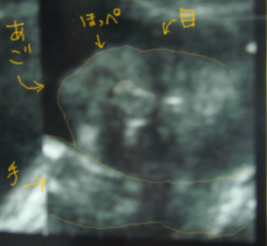

*画像は20W3Dの時のもの。退院するときの診察で撮ってもらったもの。 こっちに向かって、“元気だよ”ってレナがピースしてる見たいで思わず笑顔になった一品(^ω^)